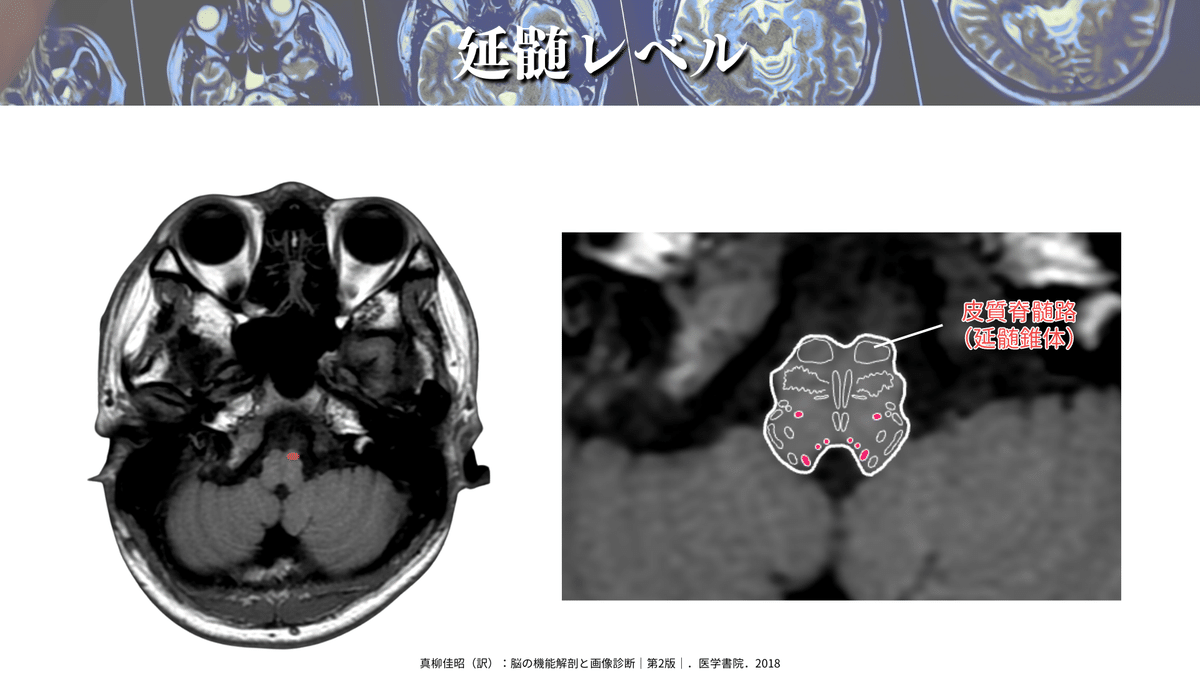

延髄レベル

詳しい場所も見ていきましょう!

CSTはよく「錐体路」と言われていますが、これはこの延髄錐体を通過するからになります👍

この錐体を通過する際に対側に交叉するので、脳とは反対側の四肢の運動を制御しているわけですね‼️

DTTで確認してみても、前方の延髄錐体を通過していることが分かりますね👍

ちなみに、延髄錐体で交叉をするわけですが、錐体交叉後に損傷された場合には損傷側と同側の運動麻痺が出現しますので、損傷レベルには注意してくださいね🙇♂️

真柳佳昭(訳):脳の機能解剖と画像診断|第2版|.医学書院.2018